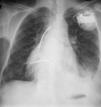

Homem 56 anos, referenciado ao nosso serviço em 1978, com o diagnóstico de cardiopatia congénita não cianótica operada: encerramento de comunicações interventricular (CIV) e interauricular (CIA) associado a correção de estenose valvular pulmonar. A radiografia do tórax mostrava mesocárdia. A partir de 1992 verificaram‐se sintomas/sinais de insuficiência cardíaca, com sopro sistólico no bordo esternal esquerdo. Nos ecocardiogramas transtorácicos (ETT) seriados detetava‐se CIV residual alta, tendo uma ressonância magnética cardíaca (RM), em 1999, colocado o diagnóstico de transposição das grandes artérias sem presença de CIV/CIA.

Em 2005, foi‐lhe implantado um cardioversor desfibrilhador (CDI) por taquicardia ventricular sincopal (Figura 1).